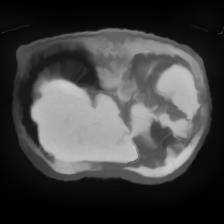

In clinical practice, well-aligned multi-modal images, such as Magnetic Resonance (MR) and Computed Tomography (CT), together can provide complementary information for image-guided therapies. Multi-modal image registration is essential for the accurate alignment of these multi-modal images. However, it remains a very challenging task due to complicated and unknown spatial correspondence between different modalities. In this paper, we propose a novel translation-based unsupervised deformable image registration approach to convert the multi-modal registration problem to a mono-modal one. Specifically, our approach incorporates a discriminator-free translation network to facilitate the training of the registration network and a patchwise contrastive loss to encourage the translation network to preserve object shapes. Furthermore, we propose to replace an adversarial loss, that is widely used in previous multi-modal image registration methods, with a pixel loss in order to integrate the output of translation into the target modality. This leads to an unsupervised method requiring no ground-truth deformation or pairs of aligned images for training. We evaluate four variants of our approach on the public Learn2Reg 2021 datasets \cite{hering2021learn2reg}. The experimental results demonstrate that the proposed architecture achieves state-of-the-art performance. Our code is available at https://github.com/heyblackC/DFMIR.